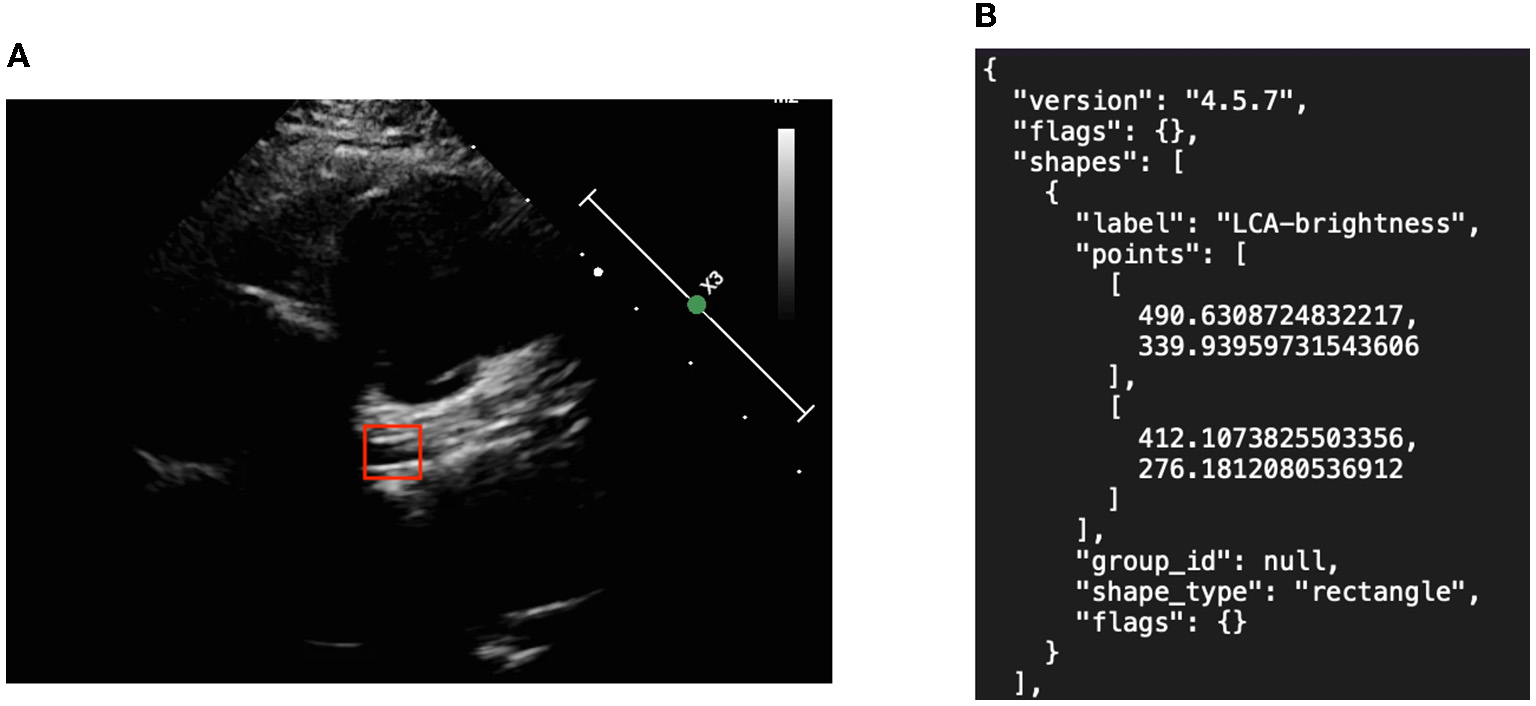

We created object detection algorithms to learn the precise location of the two major symptoms. Image annotation was required to mark the location of the aneurysm as shown in Figure 3. Subsequent algorithms were designed to read the contents of the JSON materials, including file location, disease attribute, and corresponding location. In addition, the association between data amplification method and marking results, such as the image rotation-marking frame relationship, was considered so as to maximize the advantages of data amplification.

Figure 3

Object detection picture and annotation format in JSON. (A) Left coronary artery annotation and (B) JSON file.